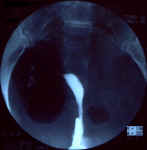

| Utérus fortement rétrofléchi, légèrement dextroposé, avec l'opacification d'une seule corne dont les contours sont réguliers. Trompe droite perméable. Conclusion:

Utérus unicorne droit, rétrofléchiTrompe droite perméable |    |